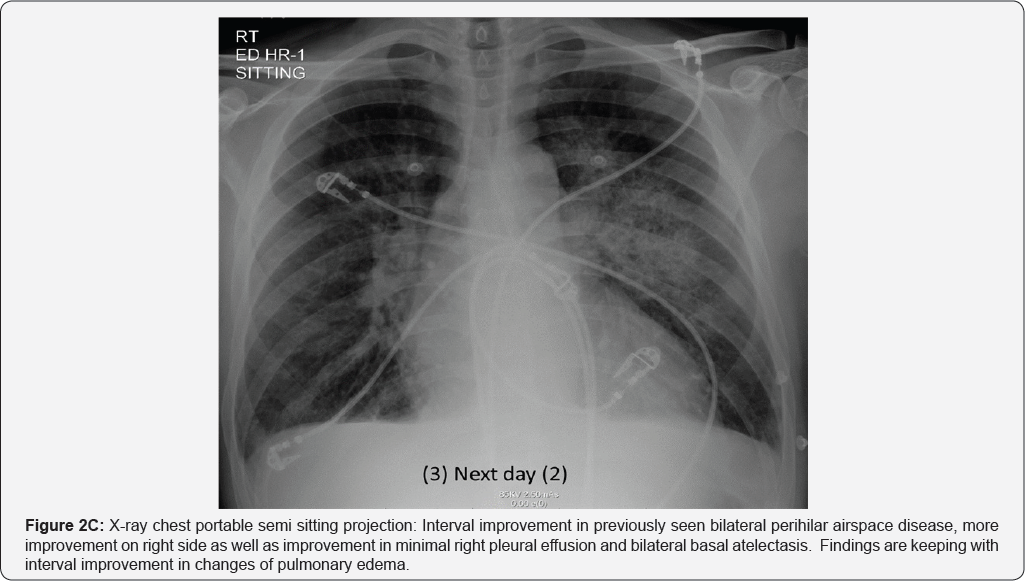

X-Rays and CT during his Hospital stay: (Figure 2A-2E)

Pleural effusion (RT>LT) multiple small mediastinal lymph nodes (arrow in image a & b), likely reactive. Bilateral perihilar airspace diffuse air space opacity and ground-glass attenuation with superimposed interlobular septal thickening and intralobular lines (LT> RT). Common differential of Crazy paving given as well as diagnosis of pulmonary edema (uncommon cause of crazy paving) given in view of history of CHF and improvement by treatment. Superimposed infection is likely in view of high inflammatory markers (Figures 3A & 3B).